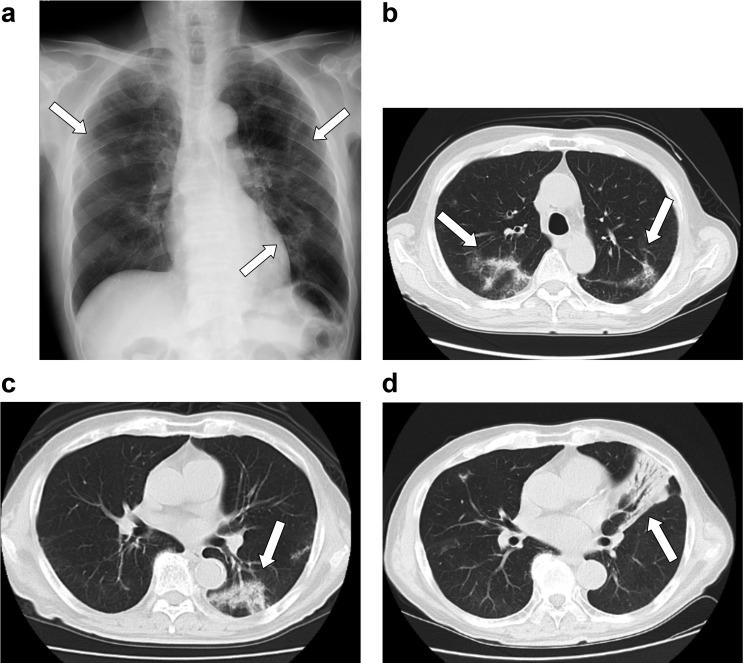

An 81-year-old man was referred to our hospital with bilateral multiple patchy opacities on chest radiography. His chief complaints were a few months' history of intermittent mild cough and slightly yellow sputum. Chest computed tomography (CT) showed non-segmental air-space consolidations with ground-glass opacities. Amyloid deposition with organizing pneumonia (OP) was seen in transbronchial lung biopsy (TBLB) specimens from the left S8. Three months later, the infiltration originally seen in the left lower lobe was remarkably diminished, and new infiltrations in the lingual and right lower lobes were detected on chest CT. Amyloid deposition with OP was seen in TBLB specimens from the left S4. Transthyretin was detected following immunohistochemical examination. The presence of wild-type transthyretin (ATTRwt) was proven using genetic analysis. The present report describes a rare case of ATTRwt amyloidosis associated with OP.

一名81岁男性因胸部X线检查发现双侧多发斑片状模糊影而转诊至我院。他的主要症状是有几个月间歇性轻度咳嗽及略呈黄色痰液的病史。胸部计算机断层扫描(CT)显示非节段性气腔实变伴磨玻璃影。在左肺下叶背段(S8)经支气管肺活检(TBLB)标本中可见淀粉样沉积伴机化性肺炎(OP)。三个月后,最初在左下叶发现的浸润明显减轻,胸部CT检测到舌叶和右下叶出现新的浸润。在左肺上叶前段(S4)的TBLB标本中可见淀粉样沉积伴OP。免疫组织化学检查后检测到转甲状腺素蛋白。通过基因分析证实存在野生型转甲状腺素蛋白(ATTRwt)。本报告描述了一例罕见的与OP相关的ATTRwt淀粉样变性病例。